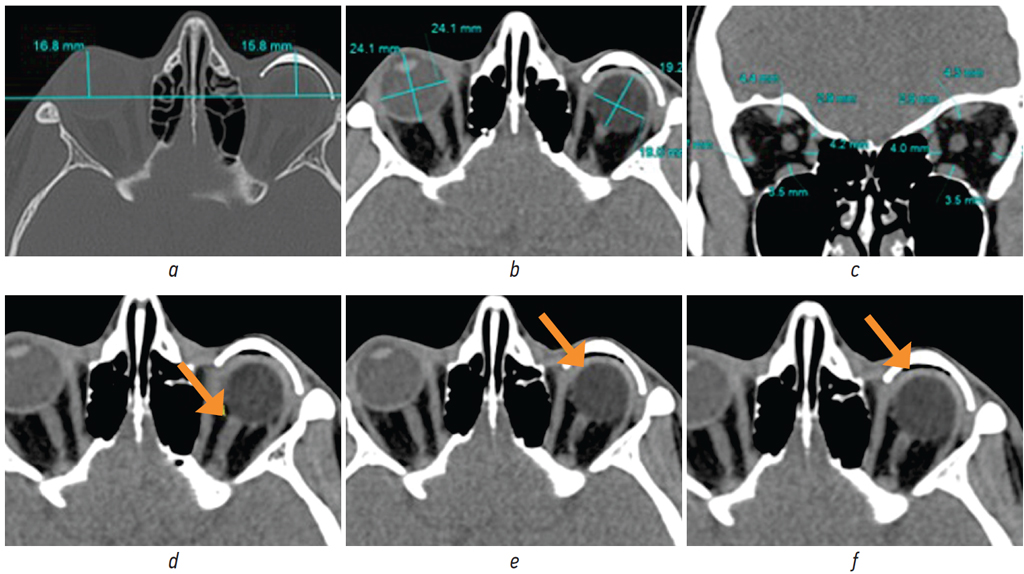

Fig. 20. MSCT of the orbit: а — axial plane, bone window mode (assessment of the symmetry of the anterior contour of the external cosmetic prosthesis and the contralateral globe using a line drawn through the zygomatico-frontal sutures on both sides and perpendiculars to this line); b — axial plane, soft tissue window mode (assessment of the globe and endoprostheses size); c — coronal reconstruction, soft tissue window mode (assessment of the symmetry and size of recti extraocular muscles and the superior oblique muscle); d–f — axial planes, soft tissue window mode [d — assessment of the optic nerve stump and the distance from the stump to the endoprosthesis (arrow); e — assessment of the endoprosthesis capsule (arrow); f — assessment of the space between the external cosmetic prosthesis and the endoprosthesis (arrow)]

Рис. 20. МСКТ орбит: а — аксиальный срез, режим костного окна (оценка симметричности выстояния переднего контура наружного косметического протеза и контралатерального глазного яблока при помощи линии, проведённой через скулолобные швы с обеих сторон и перпендикуляры к данной линии); b — аксиальный срез, режим мягкотканного окна (оценка размеров глазного яблока и размеров эндопротезов); c — корональная реконструкция, режим мягкотканного окна (оценка симметричности и размеров прямых глазодвигательных мышц и верхней косой мышцы); d–f — аксиальные срезы, режим мягкотканного окна [d — оценка культи зрительного нерва и расстояния от культи до эндопротеза (стрелка); e — оценка капсулы эндопротеза (стрелка); f — оценка пространства между наружным косметическим протезом и эндопротезом (стрелка)]